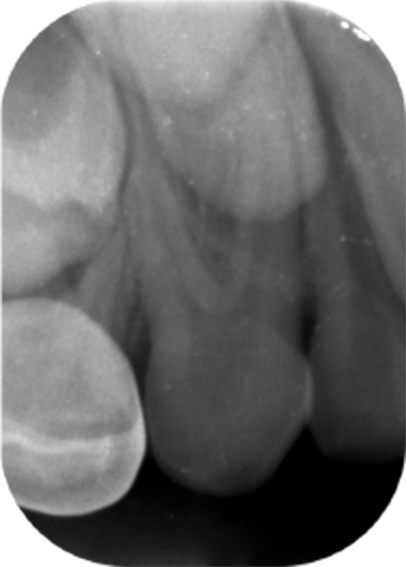

A 6-year-old Saudi male patient referred from one of the Primary Health Care centers in Dammam City to the Pediatric Dental Department at Dammam Medical Complex as a case of uncooperative behavior. The patient’s medical history did not reveal any medical illnesses. Intraoral clinical examination revealed a primary dentition with multiple carious teeth and no soft tissue abnormality was detected. Radiographic intraoral examination confirmed the clinical findings of tooth decays, and interestingly has shown a maxillary canines with two roots (Figures 1 and 2).

Figure 2. Periapical radiograph of the left maxillary primary canine demonstrating similar bifurcated root structure, indicating bilateral bi-rooted primary canines